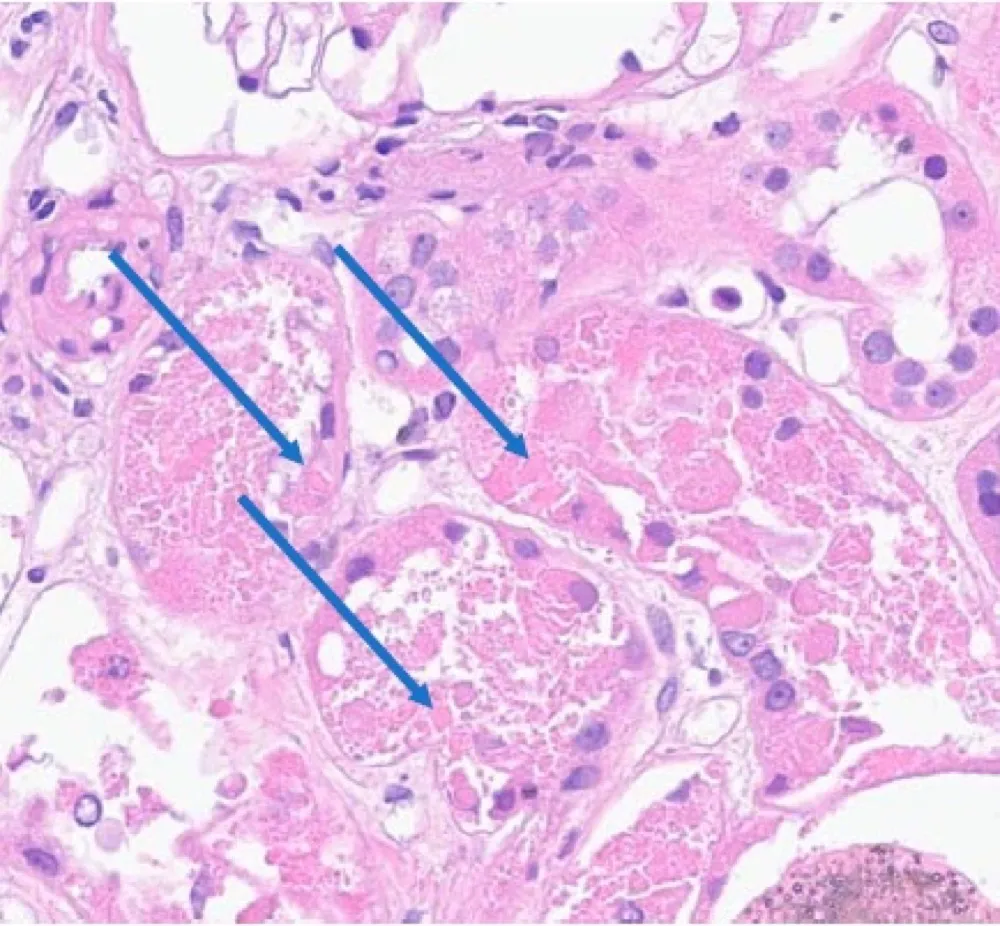

Uma causa incomum de hematúria glomerular intermitente!

Uma causa incomum de hematúria glomerular intermitente!

Hematúria pós infecção, caso clínicos para auxiliar no entendimento de causas glomerulares comuns e raras...